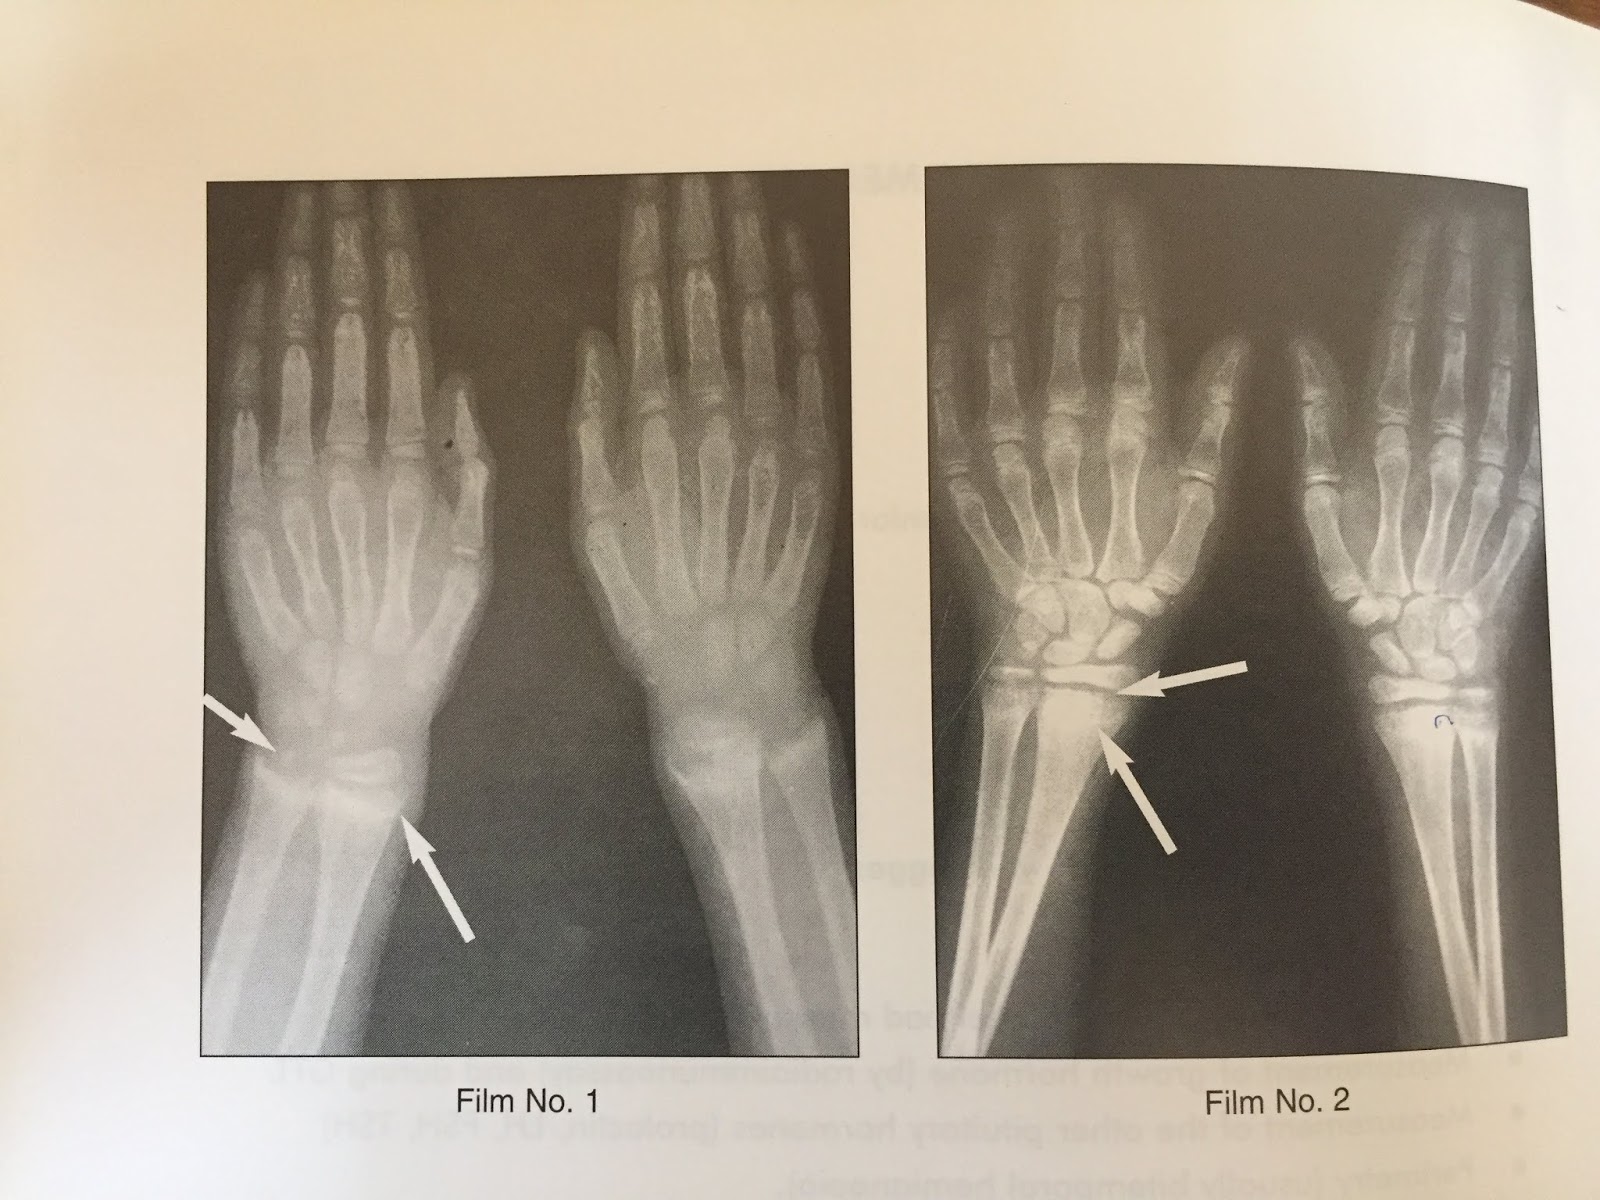

Incidental radiological diagnosis of rickets Emergency Medicine Journal

XRAYS OF RICKETS DISEASE Pigeon Chest In Rickets pectus carinatum (pigeon chest) refers to a chest wall deformity in which the sternum protrudes anteriorly. this page explains the common causes, symptoms, diagnosis and treatment of pectus carinatum (pigeon chest). pectus carinatum (also known as pigeon chest) is a condition in which, instead of being level with the ribs, the breastbone. It is less common than. Pigeon Chest In Rickets.